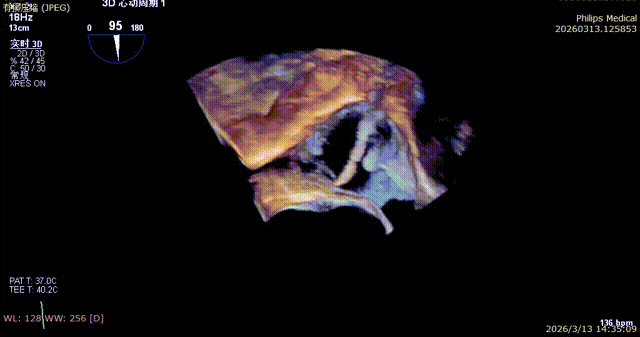

K-Clip® Tricuspid Annular Repair: Access was established via jugular vein puncture. An 18Fr delivery sheath was advanced along the stiff guidewire to the middle and inferior segments of the right atrium, and the delivery system was inserted under ultrasound guidance. The angle between the device and the annulus plane was adjusted by steering and rotation, directing the tip of the clip device toward the target sites (standard targets: No. 1: posterior‑septal commissure; No. 2: anterior‑posterior commissure). Under the ultrasound MPR‑MultiVue mode, the anchoring component was deployed at the tricuspid annulus. After stable traction, the clip arms were opened under a three‑dimensional surgical view, with orientation adjusted to appose the annulus. The anchoring component was then retracted to close the clip arms, accomplishing annular reduction. Following satisfactory procedural assessment, the clip device was released.

7. Coronary artery course and blood supply were evaluated under DSA (the course of the coronary artery was altered, but blood supply remained normal).

The first clip was initially implanted at the posterior‑septal commissure, which resulted in deformation of the coronary artery course. The first clip was released and repositioned toward the septal leaflet, with the clip arms opened to cross the posterior‑septal commissure before re‑implantation.

During implantation of the second clip, anchoring was performed at the annulus near the leaflet base. Intraoperative DSA showed no impact on the coronary arteries, and good right coronary perfusion was confirmed after deployment.